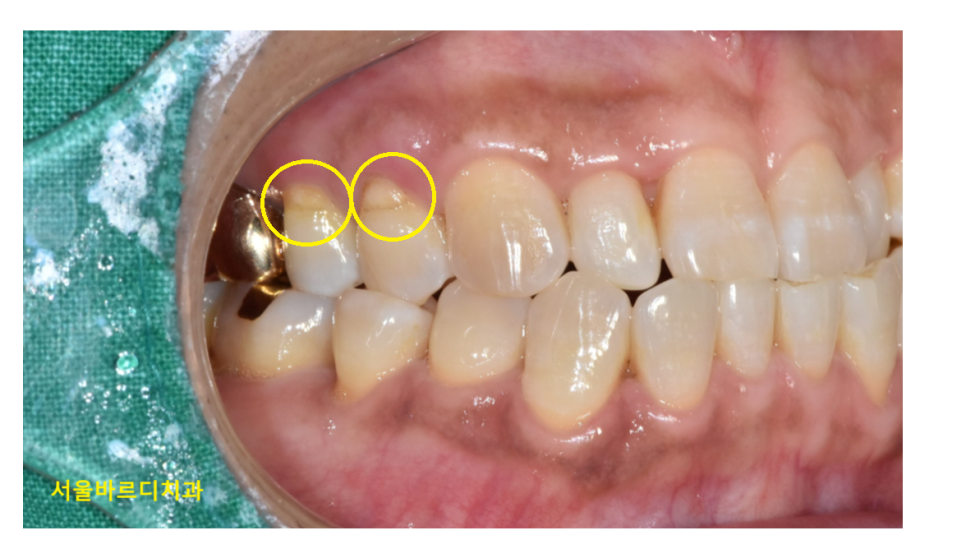

사진을 한번 봐볼까요~?

치아가 잇몸쪽 부위가 파여있죠~?

이런 증상을 우리는 치경부마모증이라고 부릅니다.

치아와 잇몸이 만나는 부분

치아의 목 부분이기 때문에 치경부라 말하는데요.

이 부위가 마모되어 치아가 깎여 나간 상태를 뜻합니다.